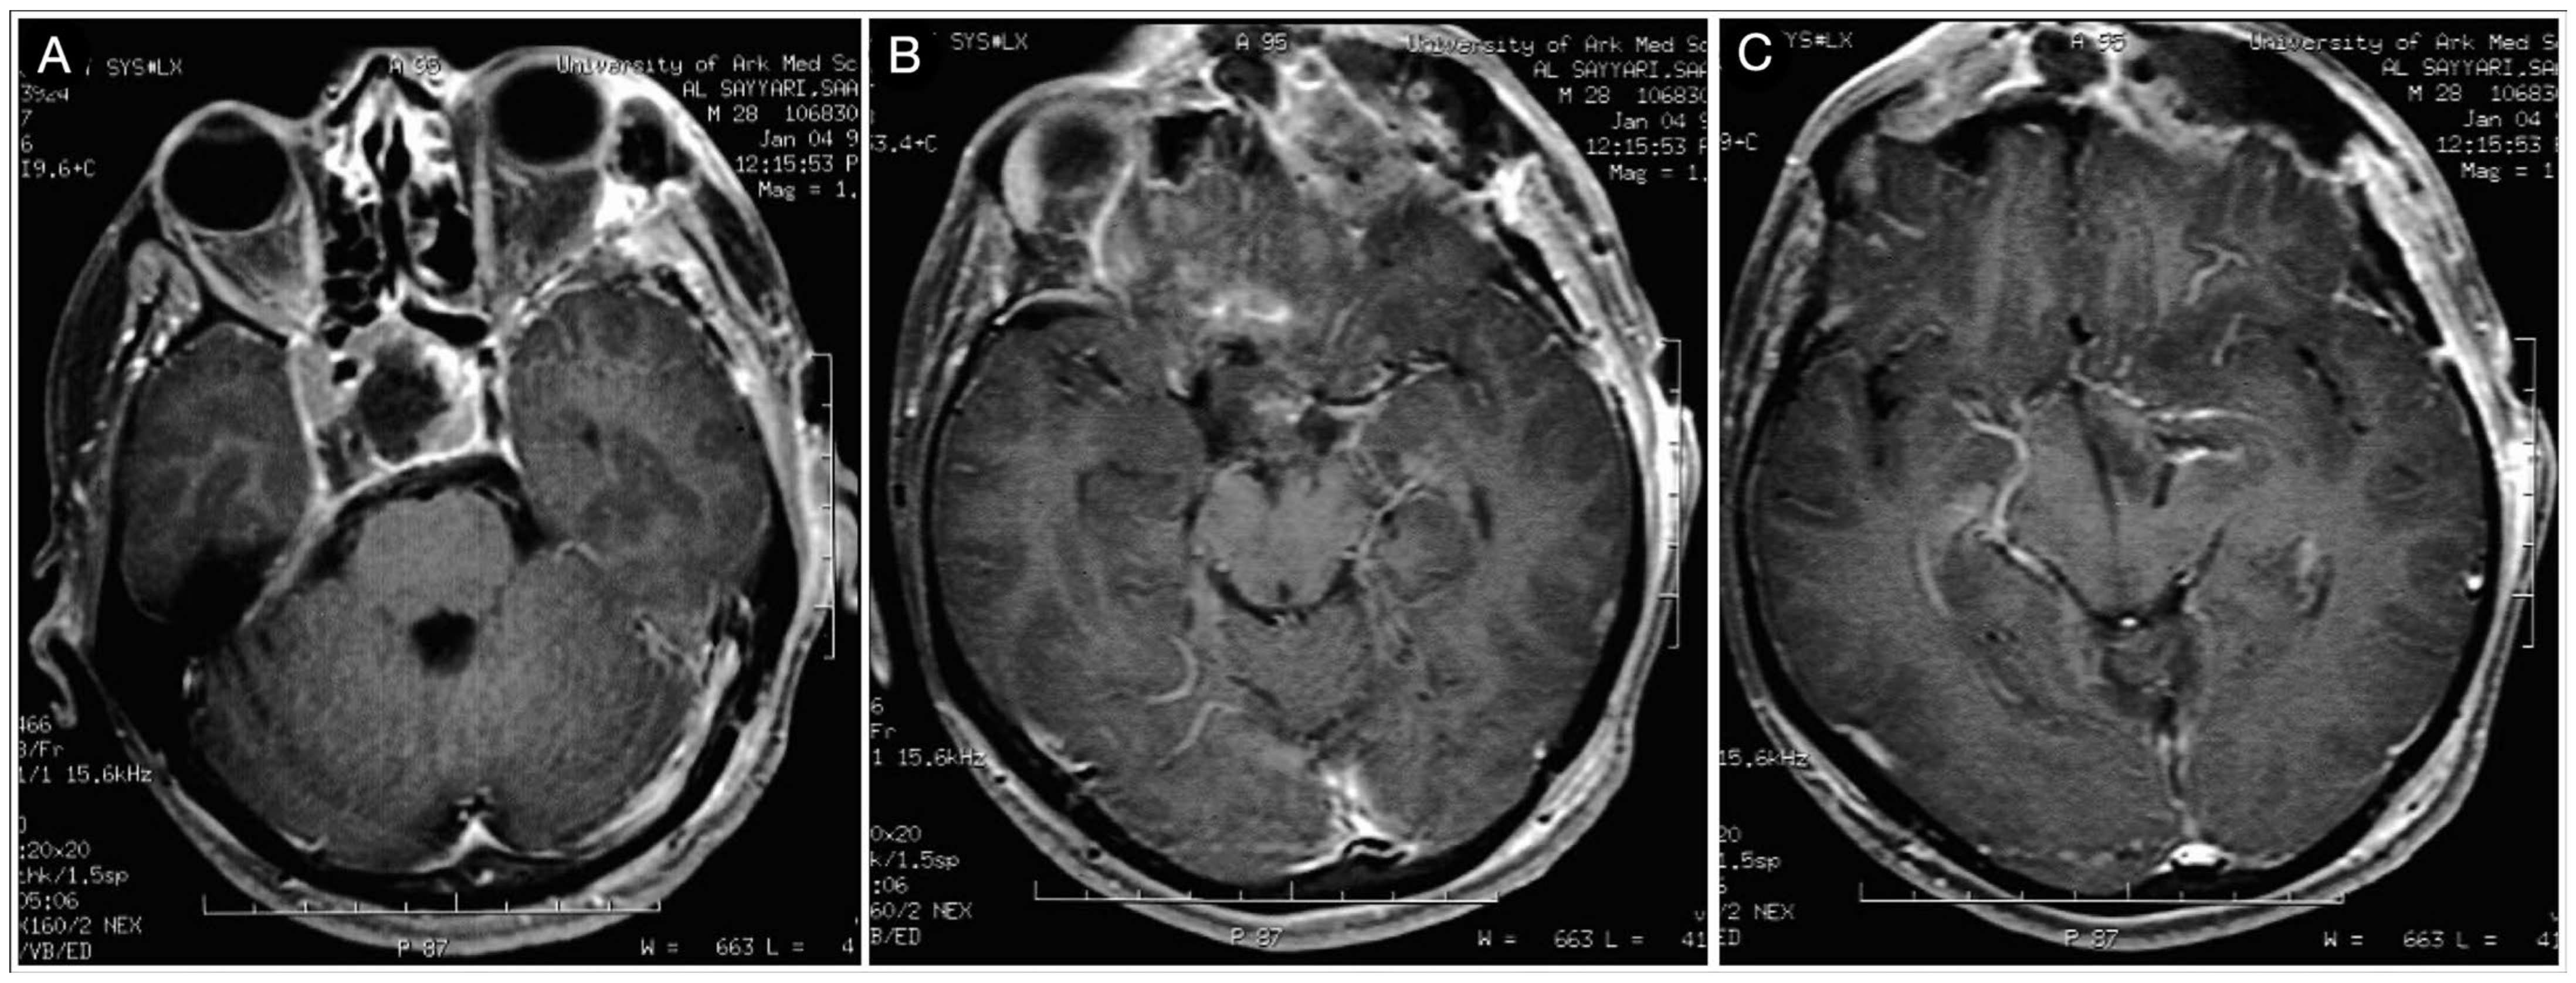

3.2.2. Case #3: Paramedian Pattern of Growth with Parenchymal Invasion

Case #8: Aggressive ACTH Tumor with Multiple Recurrences